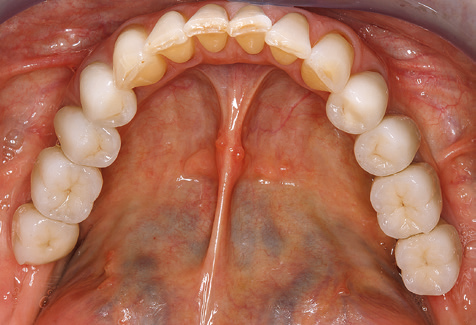

A 52-year-old patient presented in our clinic for the first time in 2004 following tooth loss in the third quadrant, expressing a desire for a new prosthetic restoration. Periodontal and radiological diagnostics revealed the need for extensive periodontological treatment. In addition, teeth 48, 28 and 27 were attributed a very poor prognosis and were subsequently extracted (Fig. 1). Following the successfully completed, systematic periodontological treatment, a fixed dental implant was inserted with the introduction of five implants in tooth regions 35, 36, 37, 46 and 47. Prosthetic treatment of the natural teeth was effected with veneered zirconium dioxide ceramic crowns; the implants were composed of two-piece, individual zirconium dioxide abutments and similarly veneered crowns made of a zirconium dioxide ceramic (Cercon base colored, Dentsply Sirona Lab). Definitive insertion of the prosthetic restoration occurred in 2005.

Due to the presence of periodontal disease, SPT was performed every three months in the first years following the insertion. The patient demonstrated a high degree of motivation and good compliance. The pocket depths recorded annually revealed a stable periodontal situation with a BOP index of below five per cent. On the basis of the stable periodontal situation and good cooperation on the patient’s part, the recall interval was extended to every six months as of the sixth year of the prosthetic function phase. Following the change in the recall interval, the respective annual documentation of the periodontal status continued to reveal a stable periodontal situation with no increase in the pocket depths and a BOP index below five per cent (Fig. 2a and b).

The ten-year check-up revealed no indications of advancing clinical attachment loss or peri-implant bone substance loss (Fig. 3).

The patient continues to visit the clinic every six months for SIT. In the following, the patient is taken as an example for demonstrating the individual working steps in a structured SPT session as it has been performed with barely any modifications over the last 12 years. Of course, some new materials and devices have been integrated into the concept over the years. This clinical case report presents the current material and device concept.

Fig. 9: The accessible implant and tooth surfaces are polished with polishing cups and suitable polishing compounds. – Fig. 10: Repeat instruction in the use of appropriate aids for oral hygiene at home should also form part of SPT. – Fig. 11a and b: Clinical situation 12 years after insertion of the prosthetic restoration. During this period, only a veneering ceramic fracture on tooth 47 and the requirement for endodontic treatment of tooth 12 were observed. All restorations are still functioning as intended.

Standardised and regular risk-adapted care in the scope of SPT is the key to treatment success for the clinical long-term success in periodontically compromised patients. This is particularly true for patients fitted with implants following successfully completed periodontal treatment (Fig. 11a and b).